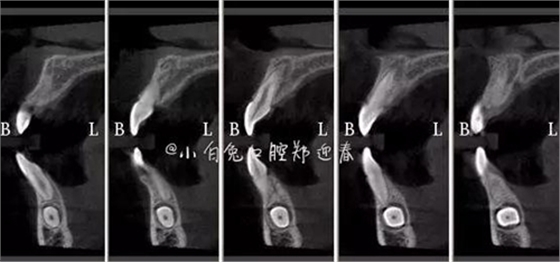

CBCT顯示